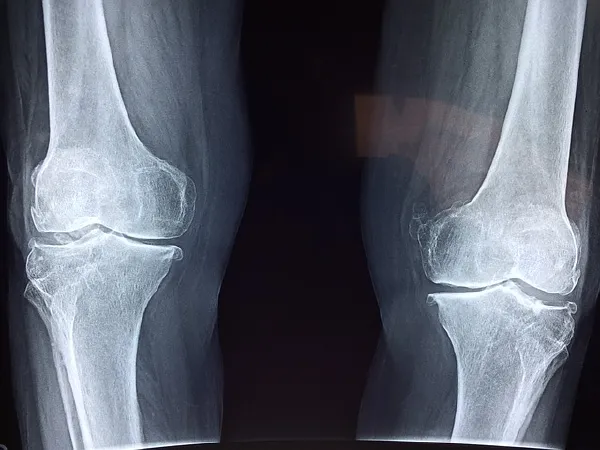

本次分享的重点是关于一位60岁的女士,她因右膝关节病接受了膝关节单髁表面置换术。也许对于许多人来说,这个手术名词有些陌生,别急,我们从头开始,带您详细了解膝关节问题以及这种治疗方法的独特之处。

在行膝关节单髁表面置换术之前,医生会对患者的情况进行全面评估,包括影像学检查(如X光或MRI)和体格检查,以确定病变范围和适应症。